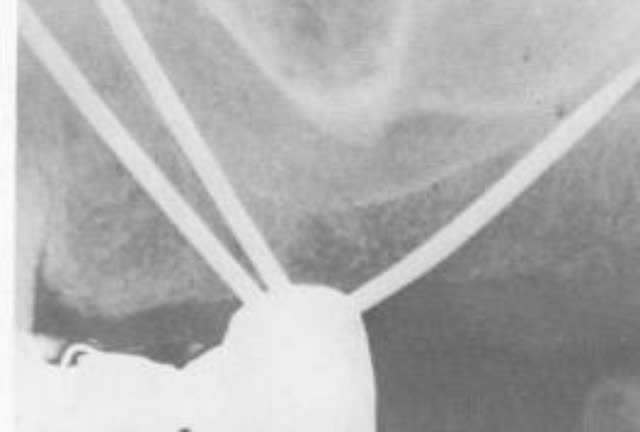

Et lĂ  c'est les Implants de Scialom En tantale puis titane : intĂ©rĂȘt on pouvait Ă©viter les structures anatomiques

Lachmar si tu regardes -> regarde la derniĂšre photo , y en a un qui a rallongĂ© un scialom 😊. Une idĂ©e de gĂ©nie ^^

D'ailleurs comment ça se mettait ? Ils les vissaient directement dans l'os ?!?!? Sans prĂ©paration avec des forĂȘts ?

sans forage, Ă  la "masse" (au maillet...;-))